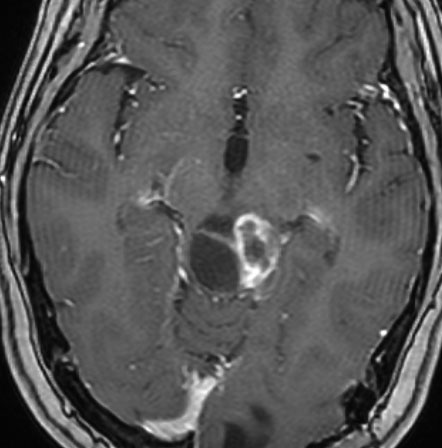

頭部打撲で検査され偶然発見された19歳男性ものです。中脳視蓋全体が腫大して腫瘍化しています。左側にのう胞があり周囲が淡くガドリニウムで増強されます。

中脳水道の癒着閉塞により,高度の停止性水頭症になっています。高身長ですが頭囲が61cmありました。小さい頃から頭が大きいので家族も気にならないようです。数年以上あるいは10年近くの長期にわたってこの水頭症は変わらないのでしょう。

頭痛などの症状はなく,眼底所見も視神経乳頭の異常はありませんでした。無治療で経過観察をしています。認知機能も全く正常で,国立大学から大学院に進む予定です。